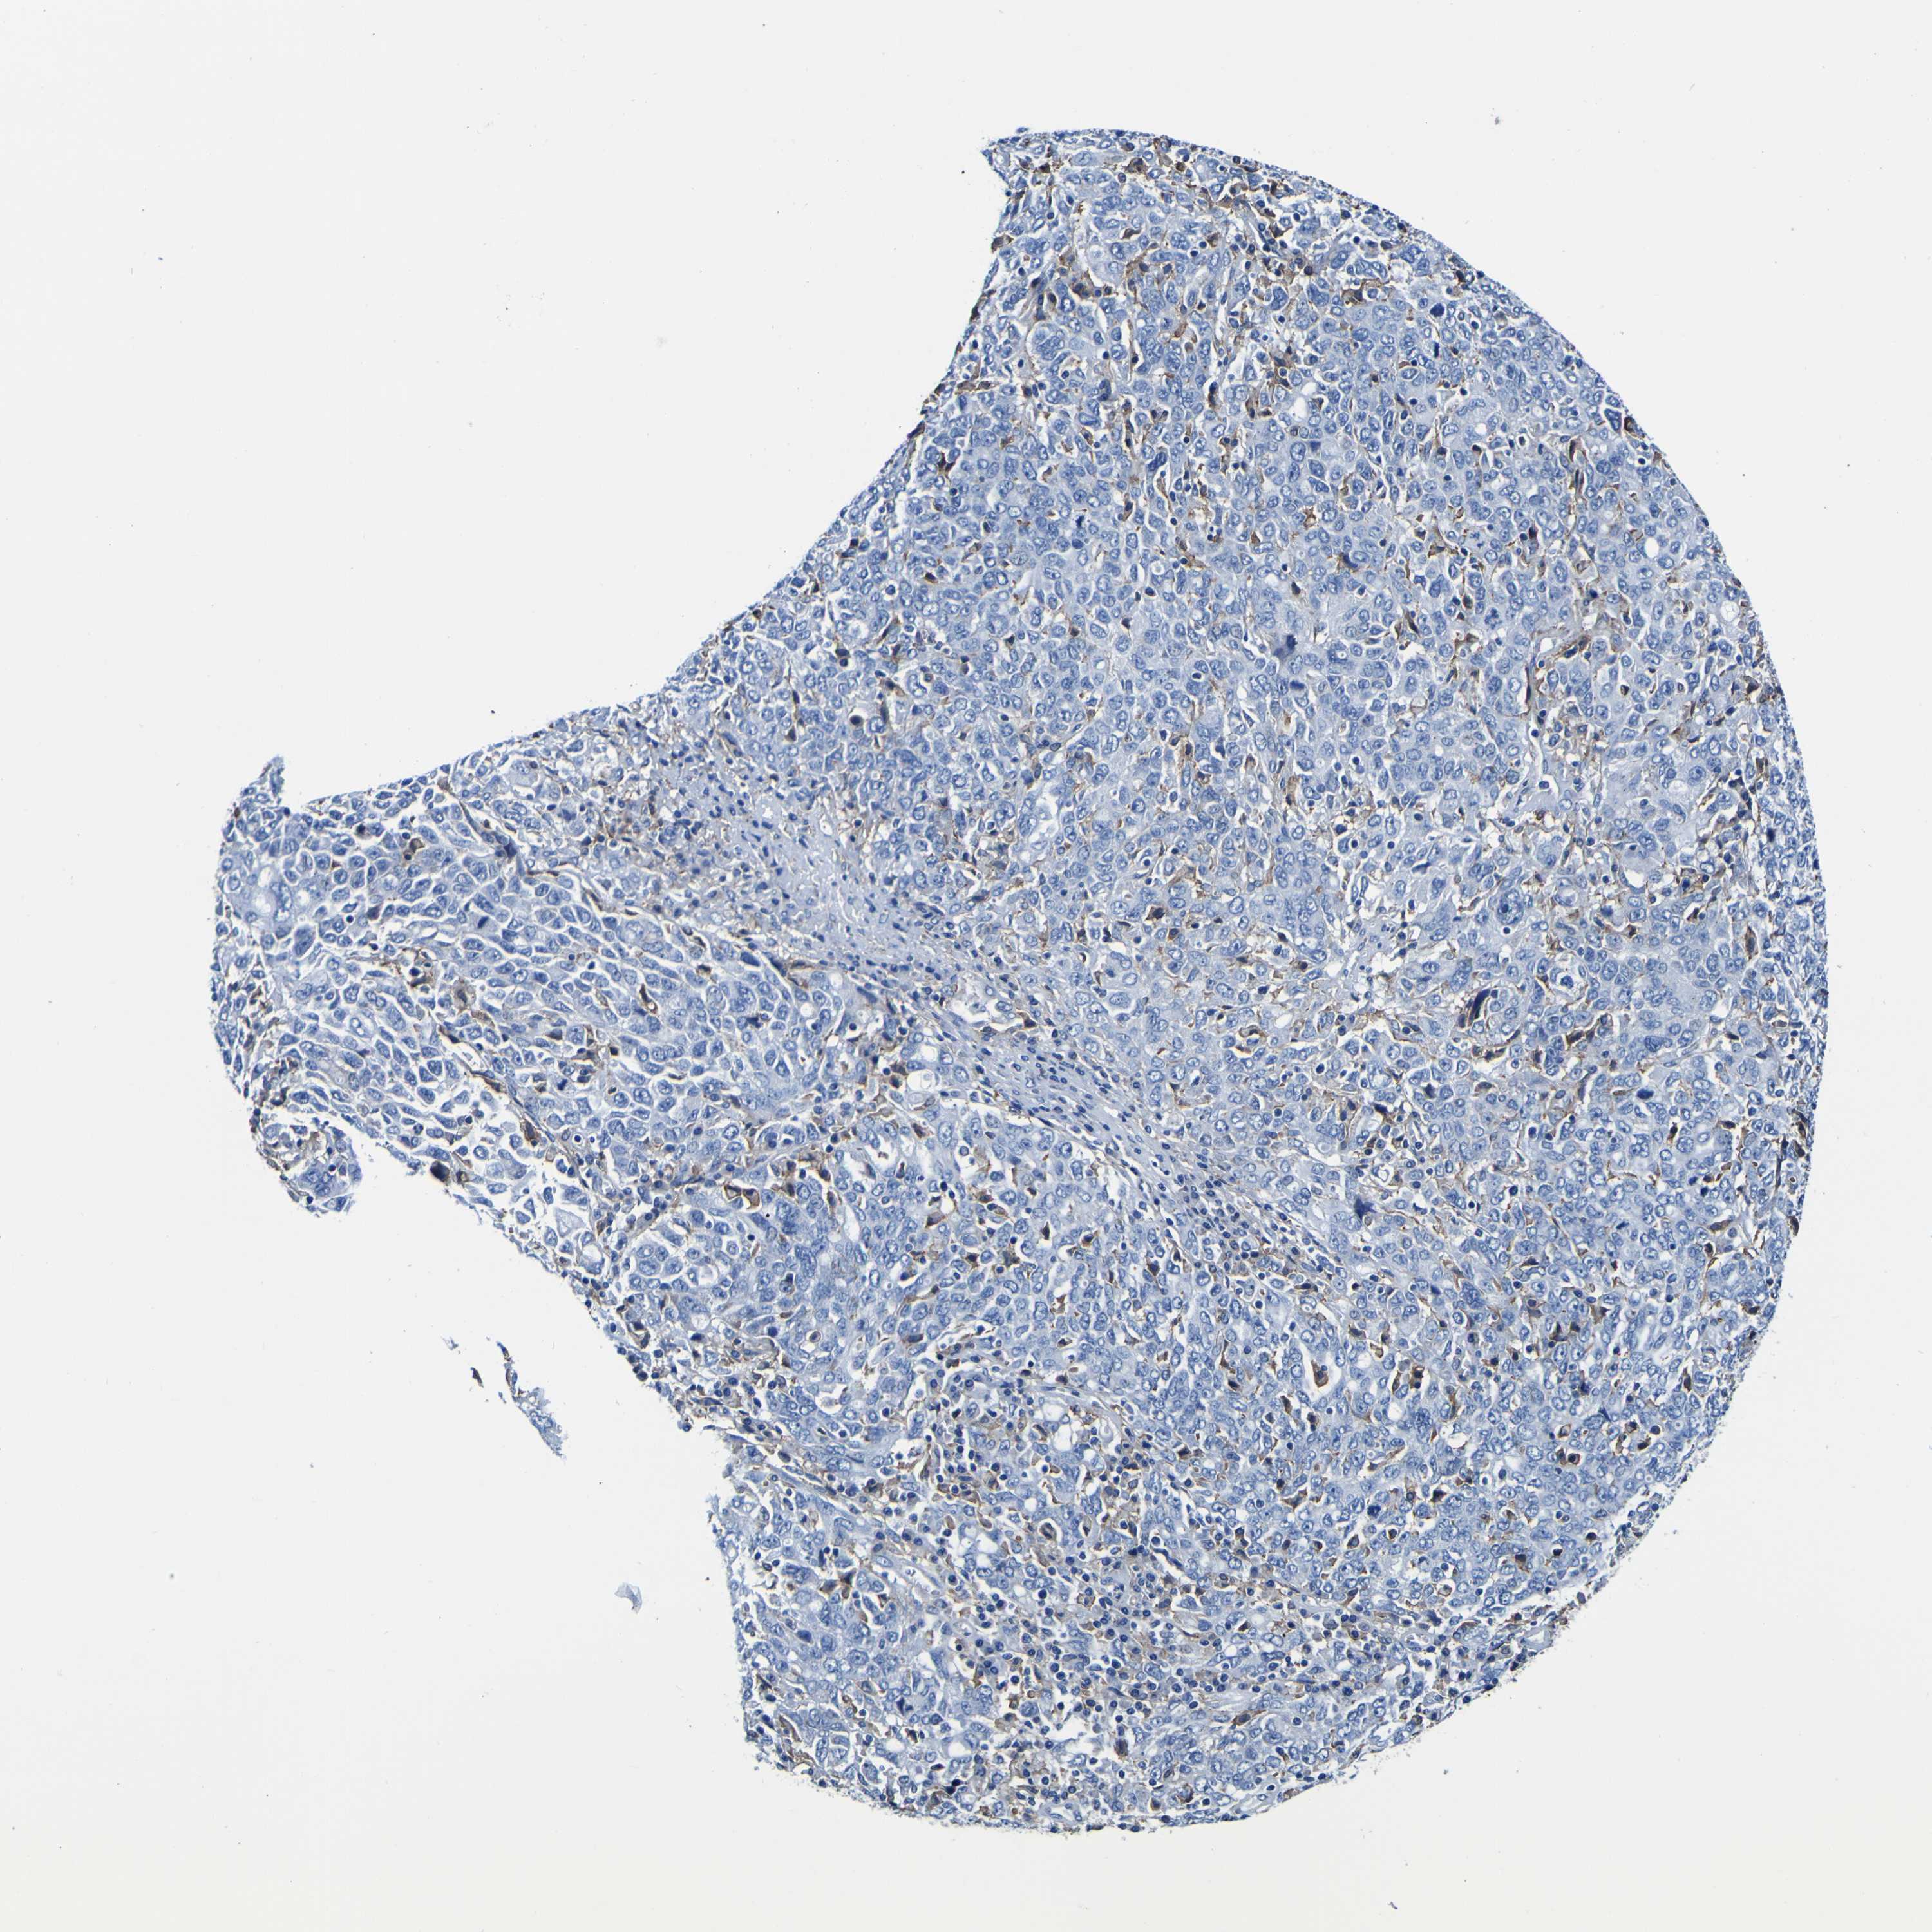

OVARIAN CANCER - Protein expressioni

A mouse-over function shows sample information and annotation data. Click on an image to view it in a full screen mode. Samples can be filtered based on level of antibody staining by selecting one or several of the following categories: high, medium, low and not detected. The assay and annotation is described here.

Note that samples used for immunohistochemistry by the Human Protein Atlas do not correspond to samples in the TCGA dataset.

Antibody stainingi

Antibody staining in the annotated cell types in the current human tissue is reported as not detected, low, medium, or high, based on conventional immunohistochemistry profiling in selected tissues. This score is based on the combination of the staining intensity and fraction of stained cells.

Each image is clickable and will lead to virtual microscopy that enables deeper exploration of all samples and also displays staining intensity scores, fraction scores and subcellular localization as well as patient and tissue information for each sample.

Antibody HPA012375

Staining

High

Medium

Low

Not detected

Intensity

Strong

Moderate

Weak

Negative

Quantity

>75%

75%-25%

<25%

None

Location

Nuclear

Cytoplasmic/membranous

Cytoplasmic/membranous,nuclear

Cystadenocarcinoma, serous, NOS

Carcinoma, endometroid

Cystadenocarcinoma, mucinous, NOS

Carcinoma, NOS